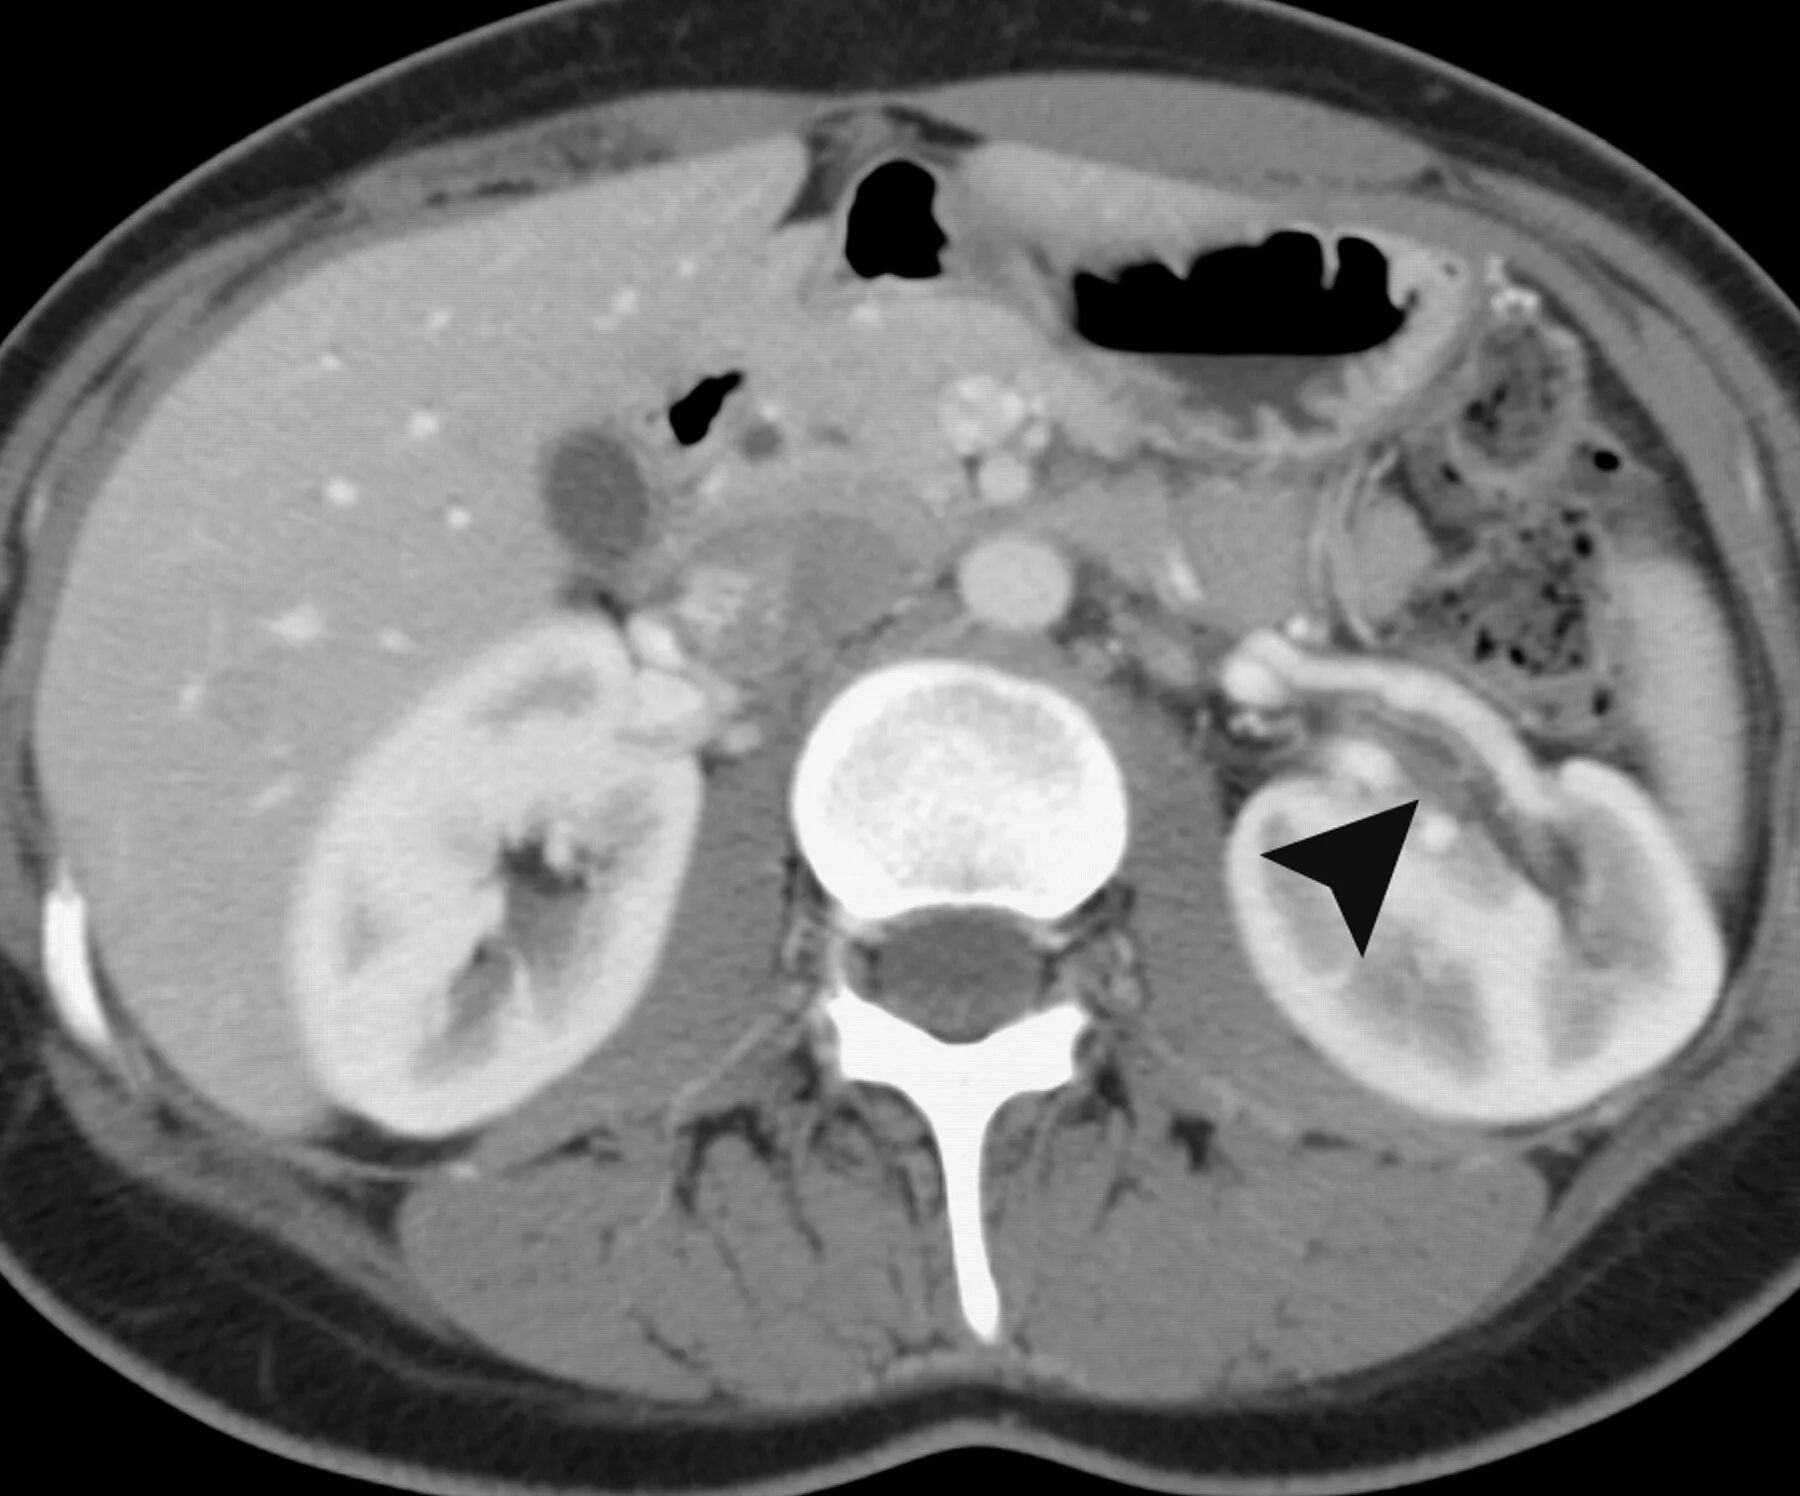

Пиелонефрит кт